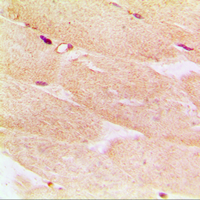

Immunohistochemical analysis of Alpha-actin-1 staining in human muscle formalin fixed paraffin embedded tissue section. The section was pre-treated using heat mediated antigen retrieval with sodium citrate buffer (pH 6.0). The section was then incubated with the antibody at room temperature and detected using an HRP conjugated compact polymer system. DAB was used as the chromogen. The section was then counterstained with haematoxylin and mounted with DPX. -